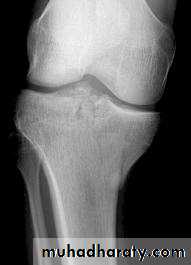

Tibial plateau fractures:Direct blow or fall from height may cause fracture of one tibial condyle or both. Fracture lateral condyle is the commonest named as bumper fracture caused by a force that abducts the tibia upon femur while the foot is fixed on ground. Patient usually is an adult, the knee joint is swollen, bruises, there is diffuse tenderness and doughy feel of haemarthrosis.ligaments injuries must be excluded.

Imaging : X-ray: anteroposterior, lateral & oblique

views. ct -Scan may used to detect amount of depression and comminuation.

Tibial plateau fracture